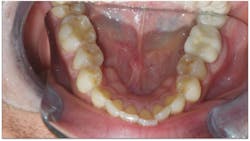

- He had improper buccolingual inclination as most of the posterior teeth had excess lingual inclination (figure 4).